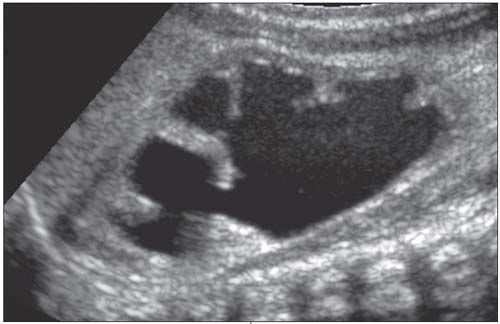

A complete blood cell count with differential shows no leukocytosis or left shift, and no anemia or thrombocytopenia. A basic metabolic panel reveals normal blood urea nitrogen, creatinine, and electrolyte levels. A renal ultrasonogram is shown.

In children with abdominal pain and suspected UPJ obstruction, ultrasonography during an acute painful episode demonstrates the abnormality (Figure); the findings are often normal when the pain subsides. In kidneys with UPJ obstruction, renal function may be significantly impaired from pressure atrophy.